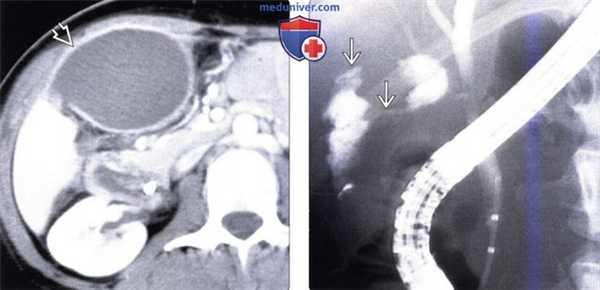

(Слева) На корональной КТ с контрастным усилением (MIP-реконструкция) у пациента, которому была выполнена трансплантация печени, определяются признаки окклюзии печеночной артерии с внезапным ее «обрывом» В возле места отхождения от чревного ствола.

(Справа) На рентгенограмме (холангиография) у этого же пациента определяются признаки ишемической холангиопатии, обусловленной окклюзией печеночной артерии, в т.ч. доминирующая стриктура общего протока, а также иррегулярность внутрипеченочных протоков. (Слева) При ЭРХПГ у пациента с желтухой после трансплантации печени определяется дефект наполнения желчного протока на уровне ворот печени, обусловленный плотной желчью; внутрипеченочные желчные протоки диффузно неравномерны. Несмотря на то, что при УЗИ признаков непроходимости печеночной артерии не выявлено, у пациента возникли тромбоз воротной вены и отторжение трансплантата.